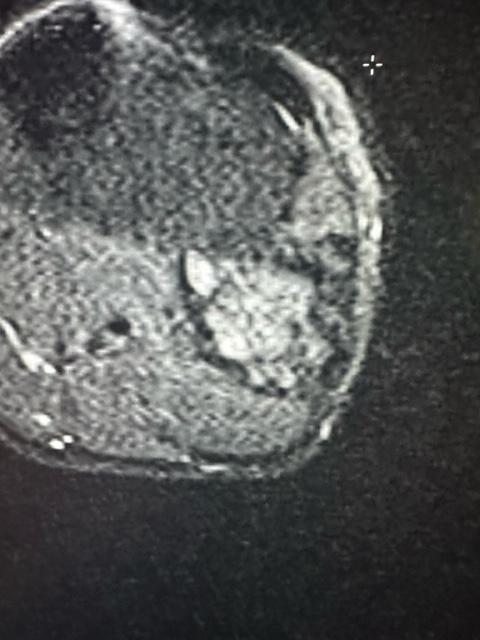

image7